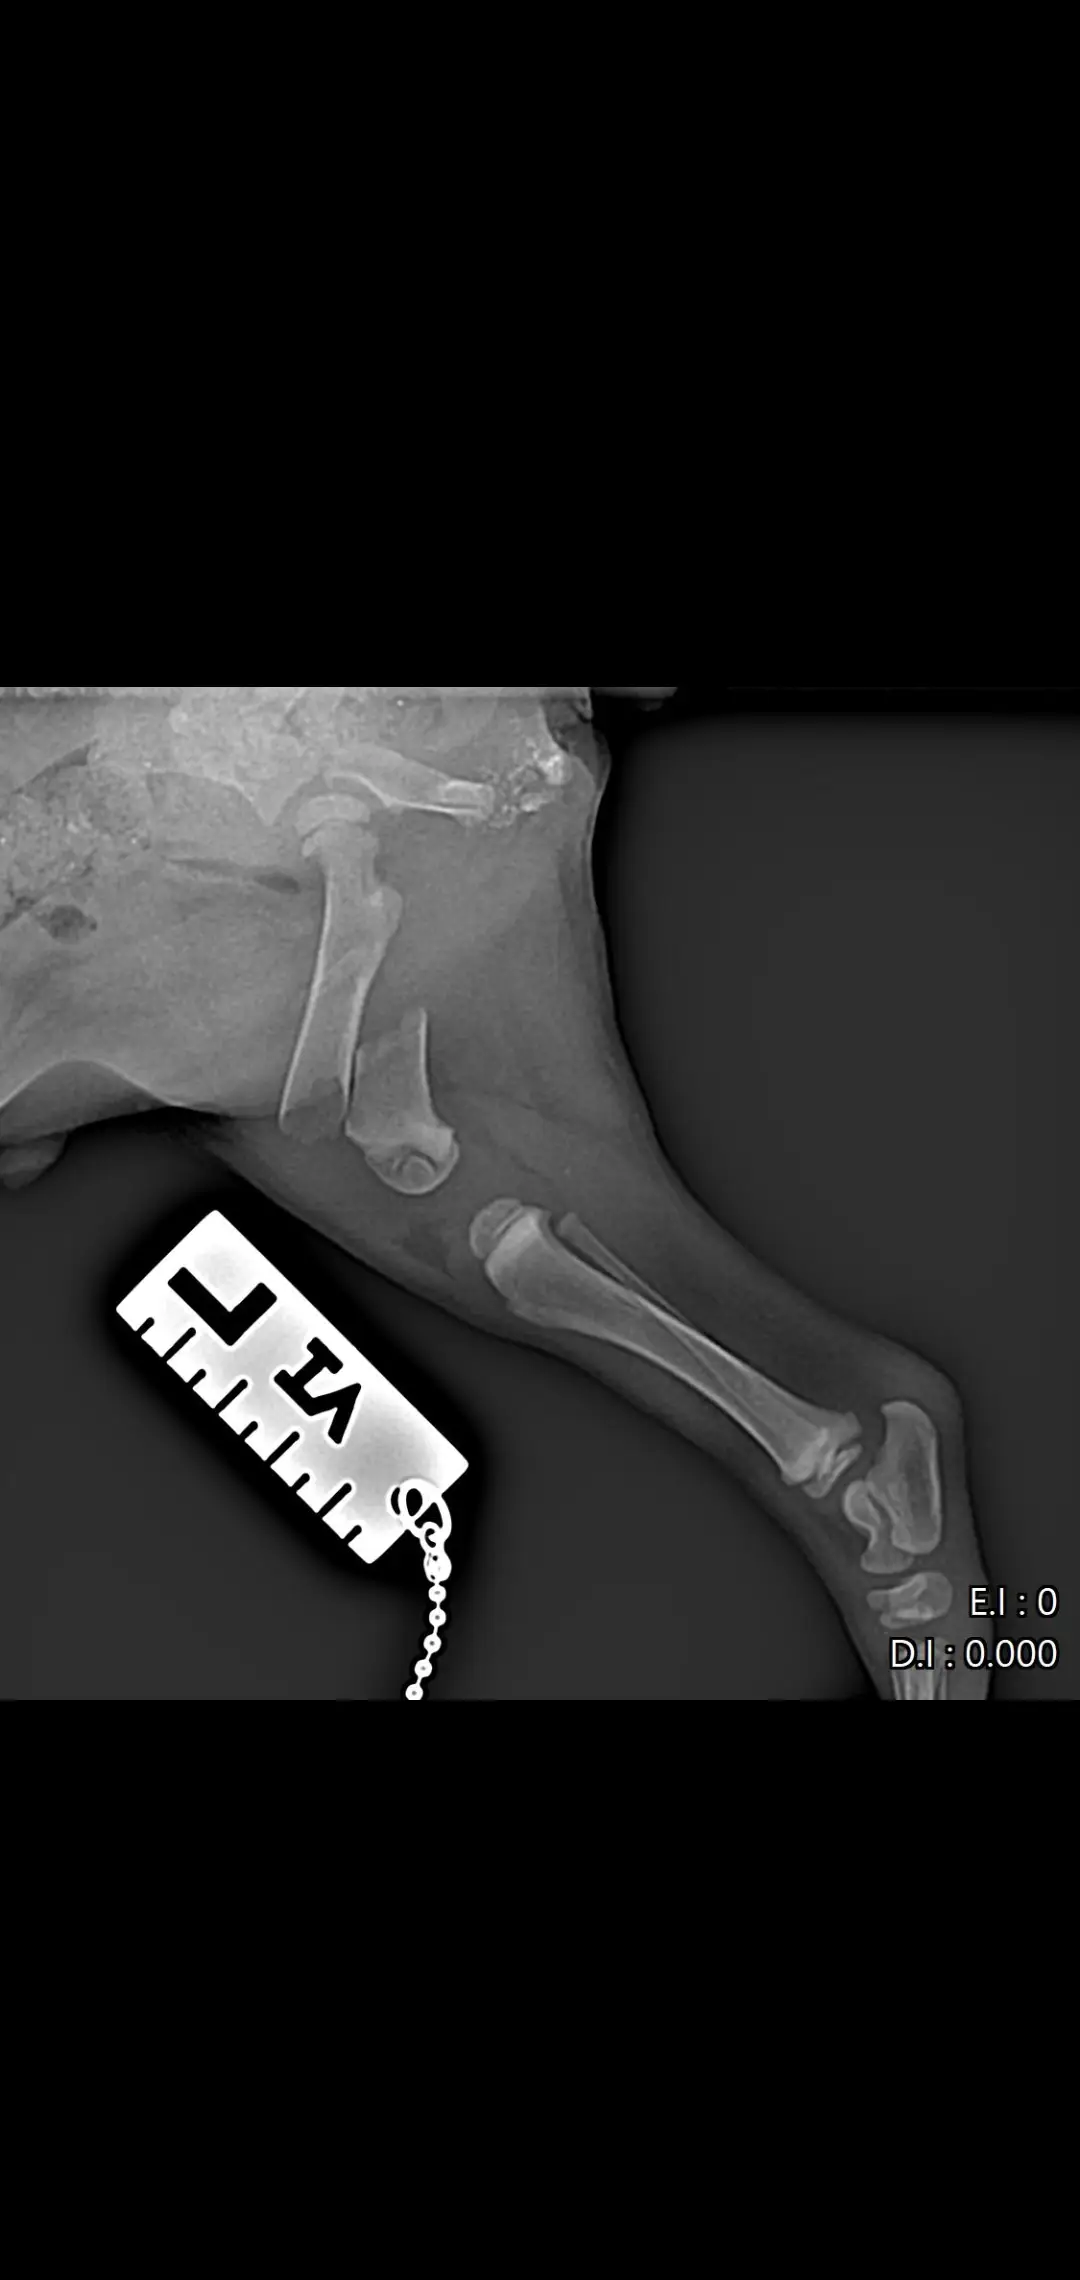

Намерих го в тежко състояние – със счупен таз и две счупени крачета. Не може да се движи, плаче при всяко докосване, но въпреки всичко се бори  да живее. 🐶😭

Бях с него във ветеринарна клиника „Провет“ в Пловдив (Тракия). Лекарят др Ташев го прегледа,оператор д-р Пачев (младши) ми каза, че има шанс да живее, но е нужна спешна операция и за двете крачета, която струва 1200 евро 😔

📸 Прилагам снимки от рентгена, за да видите колко тежко е състоянието му…плюс какво му беше изписано и направено в клиниката